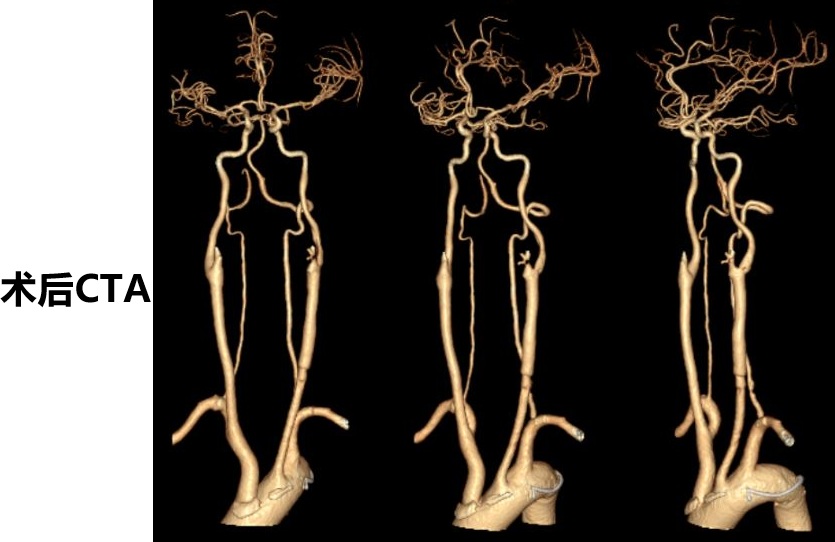

患者为机器碾压导致的复合伤,考虑外伤诱发左侧颈总动脉闭塞,导致多发脑梗死,予以去骨瓣减压手术,病情平稳后,查DSA提示:左侧颈总动脉闭塞,闭塞段位于颈2椎体至颈6椎体之间。和家属充分沟通后,行显微左侧颈动脉开通手术,手术顺利,术后患者症状明显好转,特此分享。